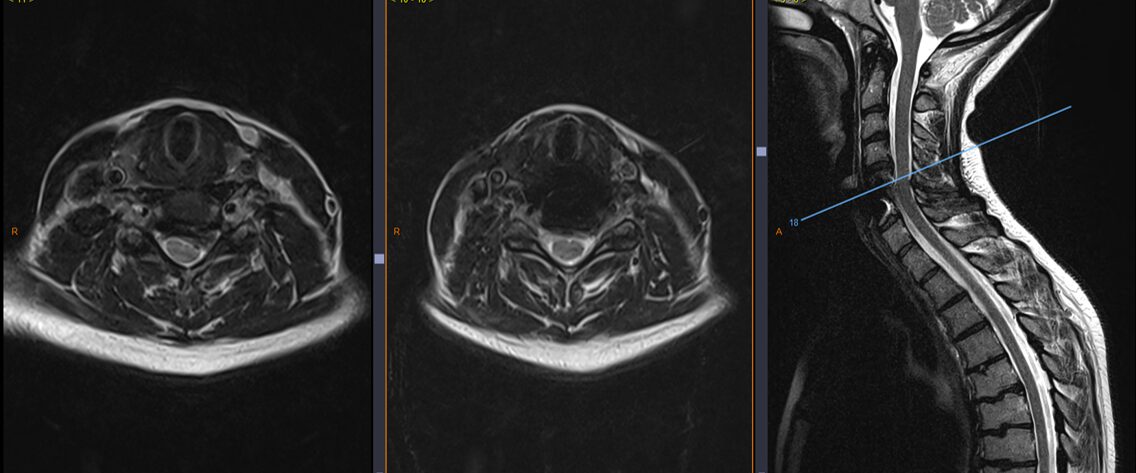

Hernie discale cervicale C5-C6 avant et après exérèse avec pose de prothèse discale cervicale